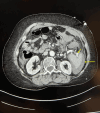

Figure 1

Figure 1. Splenic artery aneurysm (short arrow) and hemorrhage (long arrow)